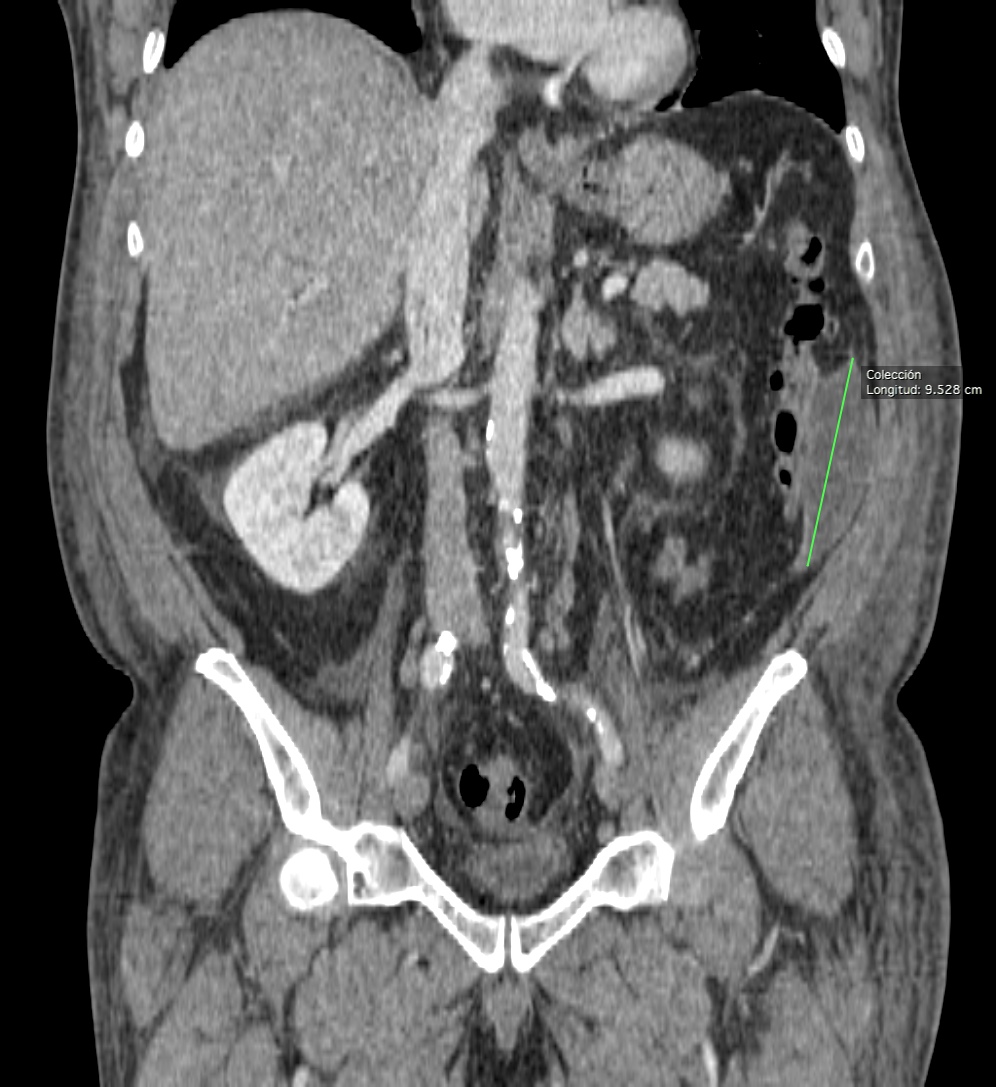

TC ABDOMEN: Se confirman los hallazgos vistos en ecografía. Se aprecia un engrosamiento mural > 4mm de un segmento aproximado de 5.5 cm de longitud con infiltración de la grasa adyacente y sin visualizar colecciones ni gas extraluminal, hallazgos compatibles con diverticulitis aguda no complicada.

CONCLUSIÓN: Diverticulitis aguda no complicada. HINCHEY grado 0

Grado 2: Absceso pélvico, retroperitoneal o distal.